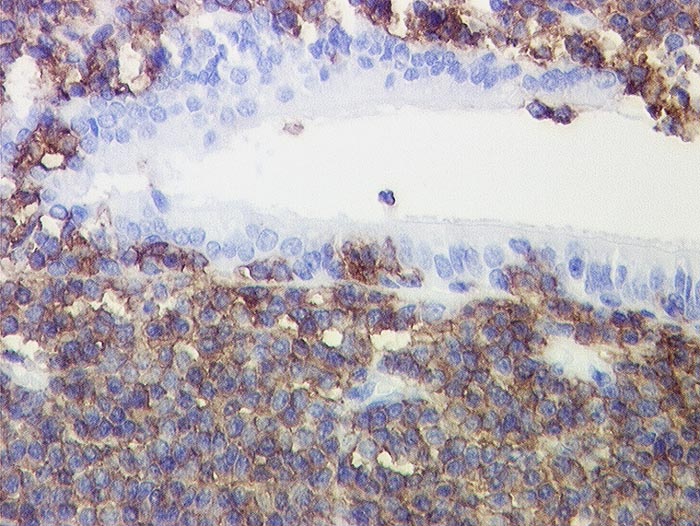

CD20

Anfärbung:

Zellmembran

Reaktion im Normalgewebe:

Pan B-Zell Marker positiv in allen B Lymphozyten, negativ in Plasmazellen.

Reaktion in Neoplasien:

Die meisten B-Zell Lymphome, etwa 50% der B Zell lymphoblastischen Lymphome und einige Myelome reagieren positiv.

Diagnostischer Nutzen:

Unterscheidung von reaktiven und neoplastischen Infiltraten zusammen mit CD3. Reaktive Infiltrate bestehen meist aus einem Gemisch von B und T Lymphozyten mit Überwiegen der T Lymphozyten. In B-Zell Lymphomen überwiegen CD20 positive B-Zellen.

Unterscheidung von B- und T-Zell Lymphomen.